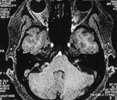

面肌痉挛疾病的成功治疗,首先是有高场强磁共振技术支持,使压迫神经的微血管在磁共振上一览无余。